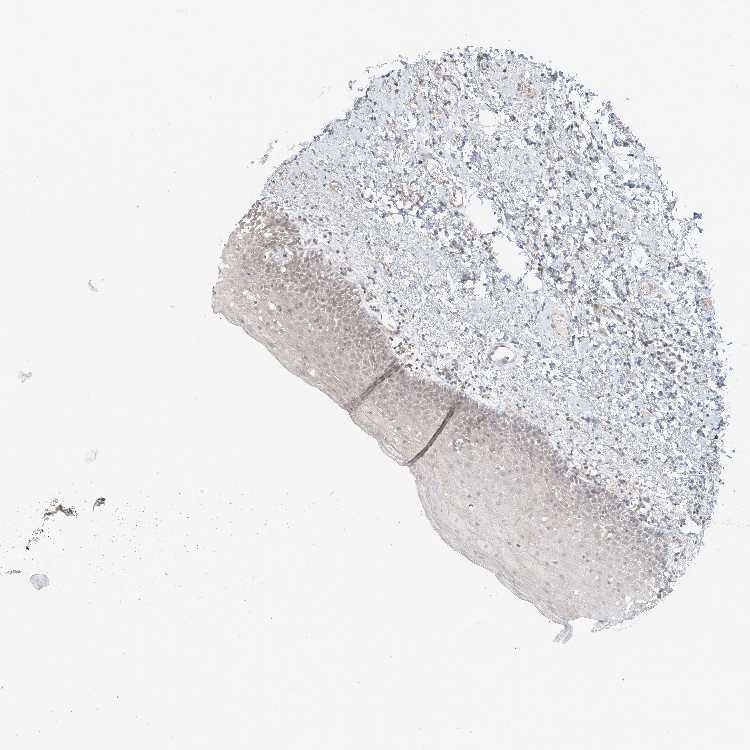

TISSUE PRIMARY DATA ORAL MUCOSA Show tissue menu

ORAL MUCOSA - Antibody stainingi

Antibody staining in the annotated cell types in the current human tissue is reported as not detected, low, medium, or high, based on conventional immunohistochemistry profiling in selected tissues. This score is based on the combination of the staining intensity and fraction of stained cells.

Each image is clickable and will lead to virtual microscopy that enables deeper exploration of all samples and also displays staining intensity scores, fraction scores and subcellular localization as well as patient and tissue information for each sample.

Antibody HPA034785Antibody HPA034786

Squamous epithelial cells Not detectedMedium